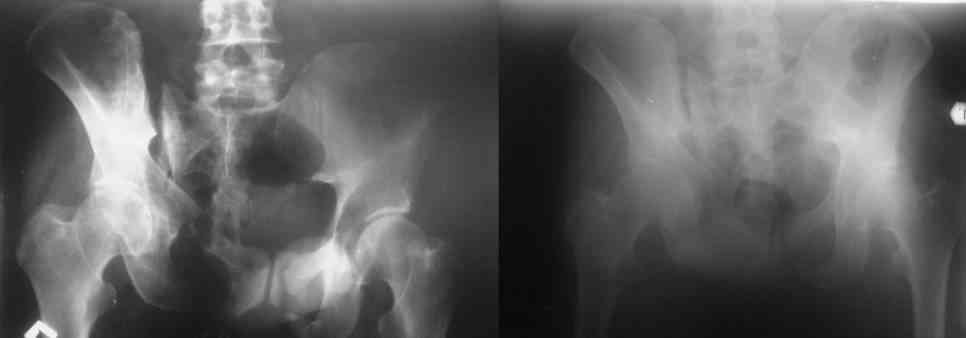

Остается только вариант закрытого аппаратного лечения. В аттаче положение отломков на вытяжении в прямой (АР) проекции. Для сравнения снимок до и во время вытяжения.

> Остается только вариант закрытого аппаратного лечения.. В аттаче

> положение отломков на вытяжении в прямой (АР) проекции. Для сравнения

> снимок до и во время вытяжения.

Только аппаратными методами в этом случае проблему не решить (фактически вы имеете дело с болтающимися псевдоартрозами), потребуется открытое вмешательство.